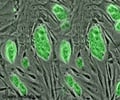

Microscopic view of Acute Lymphoblastic Leukemia